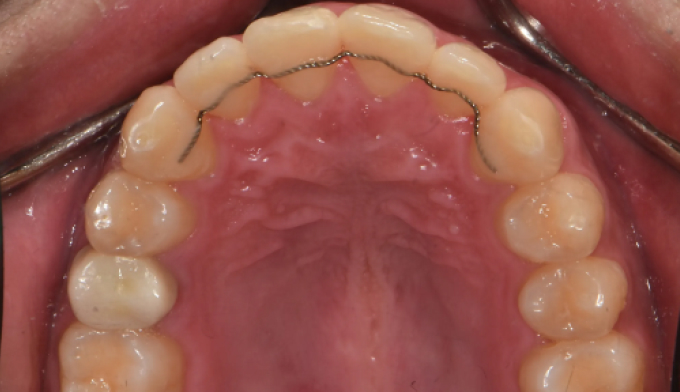

앞니불규칙

앞니를 배열하는데 있어서 필요한 공간이 많지 않은 경우, 전체교정 없이 앞니만 부분적으로 교정하는 방법을 통하여 쉽고 빠르게 치열을 가지런하게 할 수 있습니다. 멀쩡한 앞니를 삭제하고 씌우는 크라운이나 라미네이트 치료를 하지 않아도 됩니다.

교정기간은 7개월 소요되었습니다.